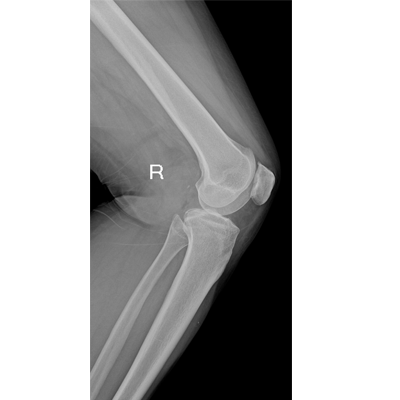

輕量化設(shè)計(jì) 小巧靈活 PLX5100

用于影像科、急診室、病房、ICU、手術(shù)室等多場景應(yīng)用。

● 數(shù)字化無線平板成像,操作簡便,成像質(zhì)量高